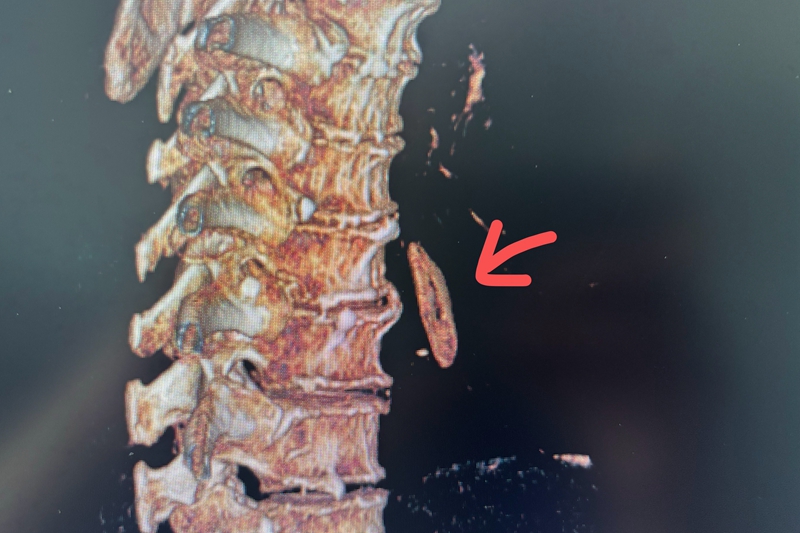

【CT三维重建】

医生进一步检查,通过CT发现张大爷的食道内有一长达2.8厘米的高信号物体,立即进行CT 三维重建,判断是一小段排骨半倾斜卡在食道中!再三追问病史,家属才想起老人当天中午就曾进食过排骨。